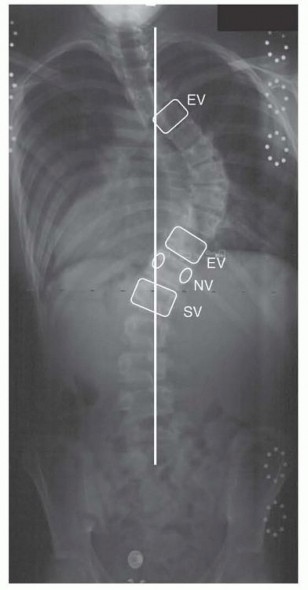

A frequently tested and clinically vital concept in spine trauma is the incidence of noncontiguous spinal fractures. When a patient presents with a primary spinal fracture, what is the rate of finding a second, separate fracture at a non-adjacent level? The literature reports this rate to be between 10% and 22%, with 15% being the most commonly cited average. This high incidence mandates that the entire neuroaxis—from the occiput to the sacrum—be imaged and scrutinized. In our patient, the whole-spine CT protocol ruled out any cervical or additional thoracic/lumbar fractures, but failing to screen the entire spine is a classic pitfall that leads to missed injuries and devastating outcomes.

- The 15% Rule: Always remember that the rate of noncontiguous spine fractures in high-energy trauma is approximately 15% (ranging from 10-22%). A complete radiographic survey of the entire spine is mandatory. Missing a secondary cervical fracture in a lumbar burst patient is a devastating, indefensible error.